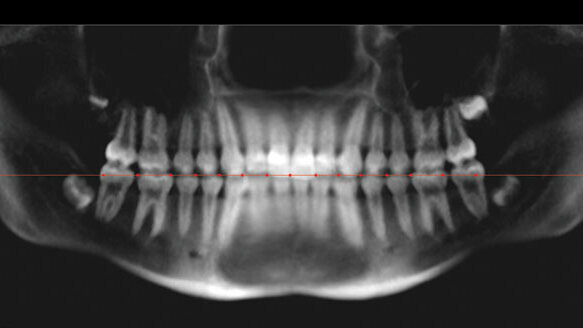

One of the major goals orthodontists try to achieve with every patient is to obtain ideal angulations and positions of all teeth at the end of active treatment. In order to accomplish this, two-dimensional (2-D) panoramic radiographs have conventionally been used to visualize both the maxillary and mandibular arches as well as root angulations.

However, because of inherent flaws in panoramic imaging, three-dimensional cone-beam computed tomography (CBCT) has been recommended to provide a more accurate and less distorted image of the dentition.

For decades, the norm in orthodontic imaging has been using 2-D panoramic radiographs to visualize the entire tooth including the root to judge the angulation of teeth.

Most orthodontists use panoramic radiographs at the start, in the middle and at the end of treatment in order to judge root parallelism to reposition brackets if necessary. This imaging technique produces a single tomographic image of the facial structures that includes both the maxillary and mandibular dental arches as well as their supporting structures.

The principal advantages of panoramic radiography are the (a) broad anatomic areas, (b) relatively low patient radiation, (c) convenience, (d) ease and (e) speed of the procedure (Sakai, 2011). Additionally, panoramic radiography is recommended by the American Board of Orthodontists to assess root angulation and parallelism as a part of the objective grading system for an orthodontist to become board certified.

However, the use of panoramic radiographs to check mesiodistal tooth angulation is fundamentally flawed primarily due to dimensional and angular distortions as a result of image layer (focal trough) discrepancy. Investigators have also attributed the inaccuracy of panoramic images to projection geometry, variable vertical and horizontal magnification factors and patient positioning errors (Bouwens, Cevidanes, Ludlow and Phillips, 2011). Part of the reason why traditional panoramic radiographs are inaccurate in capturing the angulations of teeth may be attributed to the in-orthogonal nature of the X-ray beams as the X -ray tube and the sensor move around the target, as well as the large variations in the size and shape of the dental arches (Sakai, 2011).

To overcome these problems, panoramic-like images constructed from 3-D CBCT volumetric images have been recommended. Three-dimensional CBCT images have been shown to capture the target at a 1:1 ratio with very little dimensional and angular distortions and the trough used to generate the panoramic-like images can be customized to closely follow the dental arch size and shape (Sakai, 2011).

For the construction of 2-D images, the head orientation was set to the same orientation that was used in the 3-D coordinate system with the sagittal plane equally dividing left and right, coronal plane at the maxillary molar buccal grooves and the transverse plane set at the functional occlusal plane bisecting the anterior overbite and the posterior (maxillary first molar) overbite. Two different panoramic-like images, one for the maxilla and one for the mandible were constructed for each patient (Fig. 1). The long axis was drawn through each tooth and the angle was measured against the occlusal plane using a three-point line angle tool within the Dolphin software (Fig. 2).